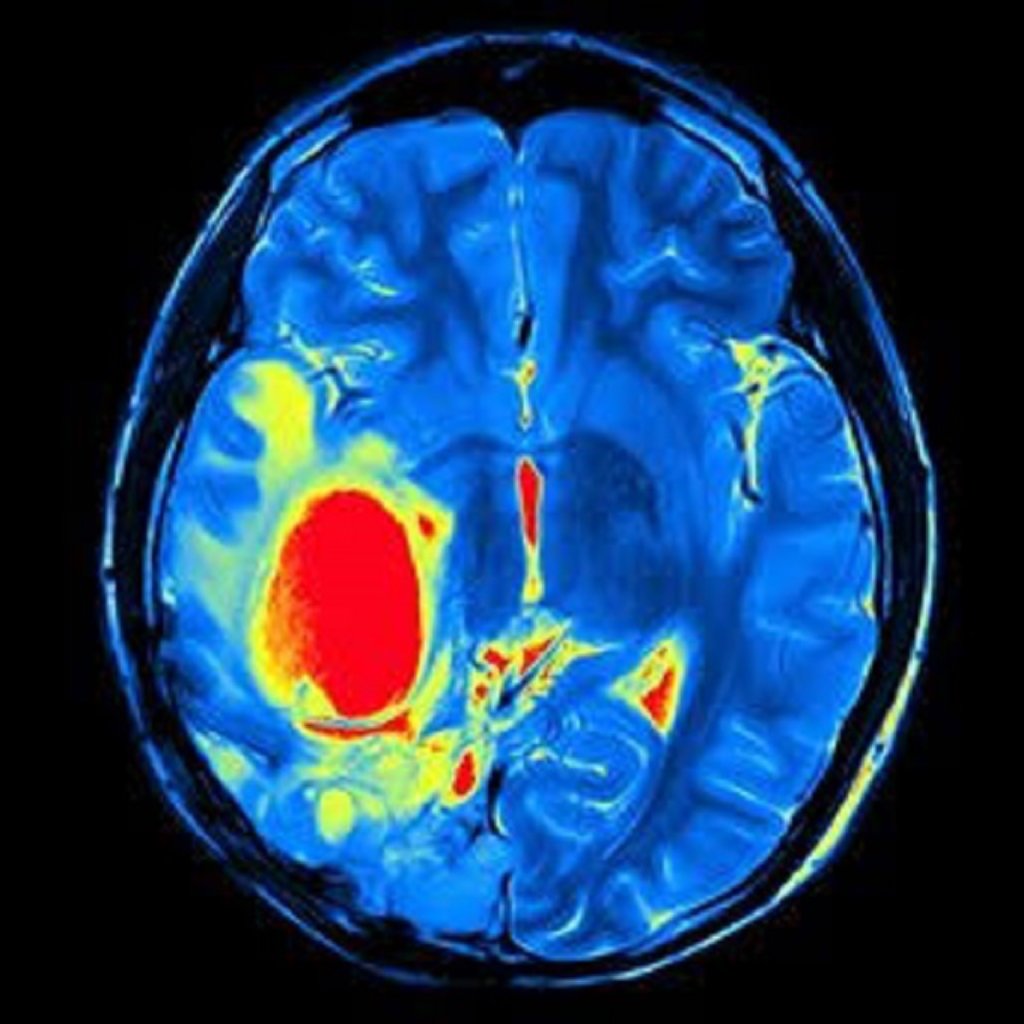

Səbəbləri Serebral qanaxmanın müxtəlif səbəbləri ola bilər: Yüksək Qan Təzyiqi (Hipertansiy ...

Şişin çıxarılması: Beyin şişlərinin müalicəsi üçün cərrahiyyə çox vaxt şişin çıxarılmasını əhatə ...